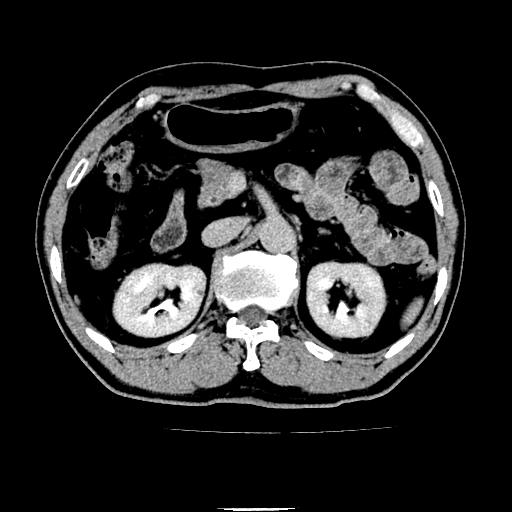

以下是引用chenqiong在2010-3-25 20:56:00的发言:[br]1、胆囊炎,胆囊息肉[br]2、肝内胆管及胆总管扩张,胆总管下端结石[br]3、十二指肠乳头旁憩室

以下是引用zxl51642在2010-3-26 10:47:00的发言:[br]胆囊炎,胆囊息肉,胆总管扩张,但未看到明显肿块,肝内胆管扩张不像恶性,炎性狭窄或阴性结石可能吧,建议mrcp,右肾小囊肿